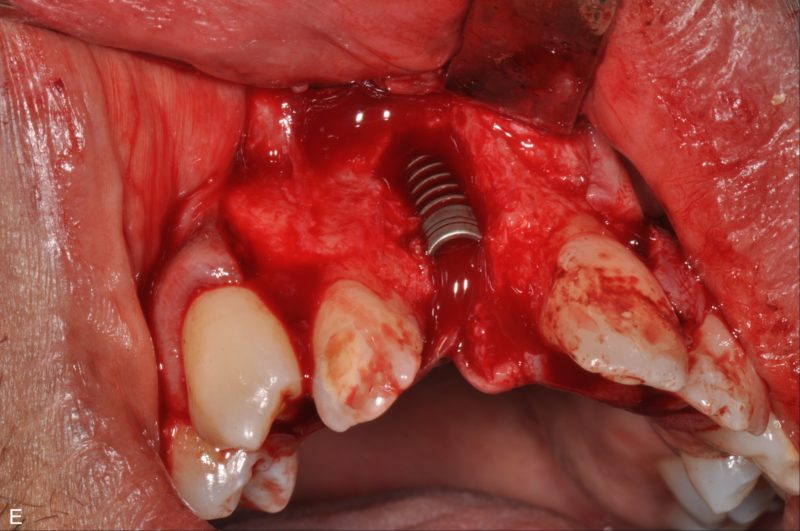

- Alergies: None

This patient have had an extraction of a central incisor and wants to restrore the aesthetic of his smile. The insertion of a 3P implant has been made with a fully open flap with lateral incisions, this approach is meant to have a better view as the vestibular plate is very thin. The implant has been inserted leaving most of the vestibular portion uncovered by bone therefore the necessity of a regenerative approach is essential for the success of the case